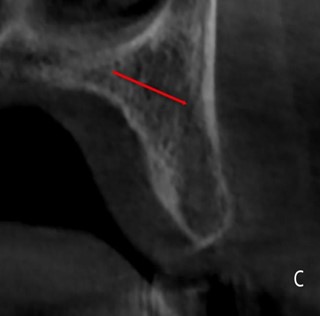

Затем мы оценили 149 визуализированных КС по их расположению в альвеолярном отростке. Установлено, что 76% КС имели нёбную локализацию, а у 12% – как центральную, так и вестибулярную (рис. 4, а, б, в). Эти данные представлены в таблице 3.

Рисунок 4. Визуализация КС в зависимости от локализации: а – небная локализация; б – центральная и в – щечная локализация.